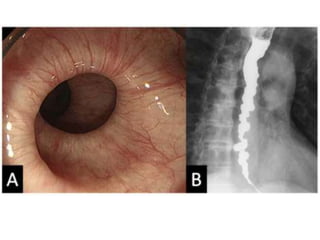

ENDOSCOPY

ESOPHAGUS

Z-LINE SQUAMOCOLUMNAR

JUNCTION

Z- Line